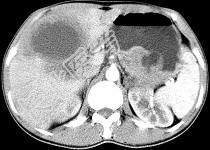

单项选择题女,61岁, 上腹部疼痛一个月,食欲减退, 消瘦,CT所见如图, 最可能的诊断是 ( )

A、肝脓肿

B、肝转移瘤

C、胃癌肝转移

D、肝包虫病

E、原发性肝癌